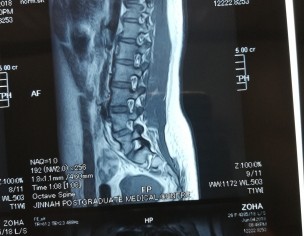

Attaching my MRI reports (MRI was in July). Everyone told me there is nothing serious just go for painkillers and physiotherapy. I was taking naproxen and was on physiotherapy from last 2 months. But still, there is no improvement. Sometimes I face severe back pain. So can someone please guide me what to do now? Please don't suggest me any treatment which is expensive as already invested a lot but all in vain. Is this disc herniation? Is it curable? I am seriously worried about it.